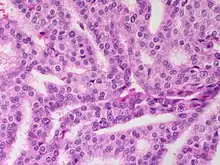

Microscopic histopathological analyses of SPC lesions (refer to adjacent high-power photomicrograph) generally show tumors with multiple circumscribed nodules of expanded ducts filled with neoplastic epithelial cells which may appear spindle-shaped or plasma cell-like, have red to pink cytoplasm due to the uptake of eosin after staining with hematoxilin & eosin, and eccentrically-placed nuclei. Rarely, signet ring-shaped cells are present. The tumors may have cystic and hemorrhagic areas. Myoepithelial cells are found within and at the periphery of these tumors. The papillary architecture seen in the other SCB types is in general not apparent; rather, pseudo-rosettes (i.e. radial arrangements of neoplastic cells around small blood vessel) and nuclear palisading (i.e. parallel arrangements of the nuclei in rows of tumors that resembles picket fences) around stromal cores (i.e. supporting tissues) may be seen. SPC tumor tissues typically (>50% of cases) have areas of neuroendocrine differentiation. The presence of these areas strongly supports the diagnosis of SPC.[21] The signet ring-shaped cells in these tumors contain cytoplasmic mucin-containing vacuoles which push their cells' nuclei to one side.[10] Mucin may also occur outside of cells in these lesions. The presence of signet ring-shaped cells bearing mucin-containing vacuoles with or without extracellular mucin strongly supports the diagnosis of SPC. SPC is considered invasive when the tumor nests have a characteristic jigsaw growth pattern with ragged and irregular margins with the loss of myoepithelial cells at the site(s) of invasion.[21] Rarely, invasive SPC occurs with nearby invasive carcinoma of NST, lobular carcinoma, cribriform carcinoma, or tubular carcinoma breast tumors.[3]

Since many of the earlier published cases of IPC actually appear to be variants of invasive EPC or SPC, there is little consistent pathological data on IPC.[7] Studies on the microscopic histopathology of IPC have reported finding (refer to the adjacent high-power photomicrograph): 1) blunt papillae or ductal structures consisting of neoplastic epithelial cells surrounding a fibrovascular core;[1] 2) papillae located in dilated ducts and variably sized microcysts plus foci of necrosis (i.e. dead cells);[4] 3) tumors totally dominated by fibrovascular cores covered with neoplastic epithelium cells;[3] and 4) tumors showing >90% papillary morphology invading nearby breast tissue and/or sub-mammary chest muscles.[22] Studies do agree that IPC tumors have, by definition, one or more sites that have invaded nearby breast and/or muscle tissue, lack myoepithelial cells at their invasion sites, and generally lack a peripheral fibrous capsule; these features are important for diagnosing IPC.[6][7][20][22] Rarely, ductal carcinoma in situ lesions are present near IPC.[3] A retrospective histopathological analysis of the tumor tissues in 1,147 individuals with IPC reported that 89.3%, 83.4%, and 2.4% of the cases had tumor cells which respectively expressed the estrogen receptor, progesterone receptor, and HER2/neu protein (however, 46.4% of the cases were not tested for the HER2/neu).[1] In a second histopathological study of 44 individuals diagnosed with IPC, 72.7% had tumor cells that expressed the estrogen receptor, 72.7% had tumor cells that expressed the progesterone receptor, and 13.6% had tumor cells that expressed the HER2/Neu protein.[22] No specific genetic alterations have been as yet been clearly associated with the tumor cells in individuals diagnosed with IPC.[6]